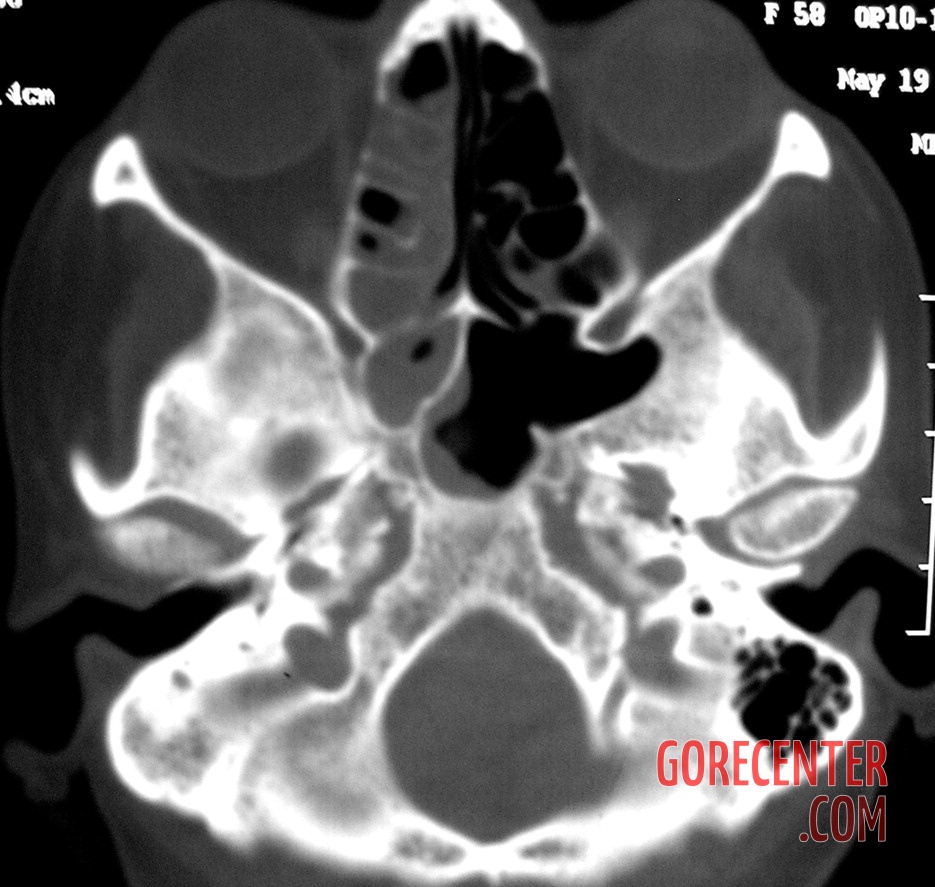

Further examinations, including blood tests, did not reveal diabetes or other common conditions that could explain the symptoms. However, it was evident that the body was fighting a severe infection. A crucial turning point came with a CT scan, which revealed extensive damage to the maxillary bone and spread of inflammation into the paranasal sinuses, including the deeper ones. Fortunately, the brain and eye sockets were not yet affected.